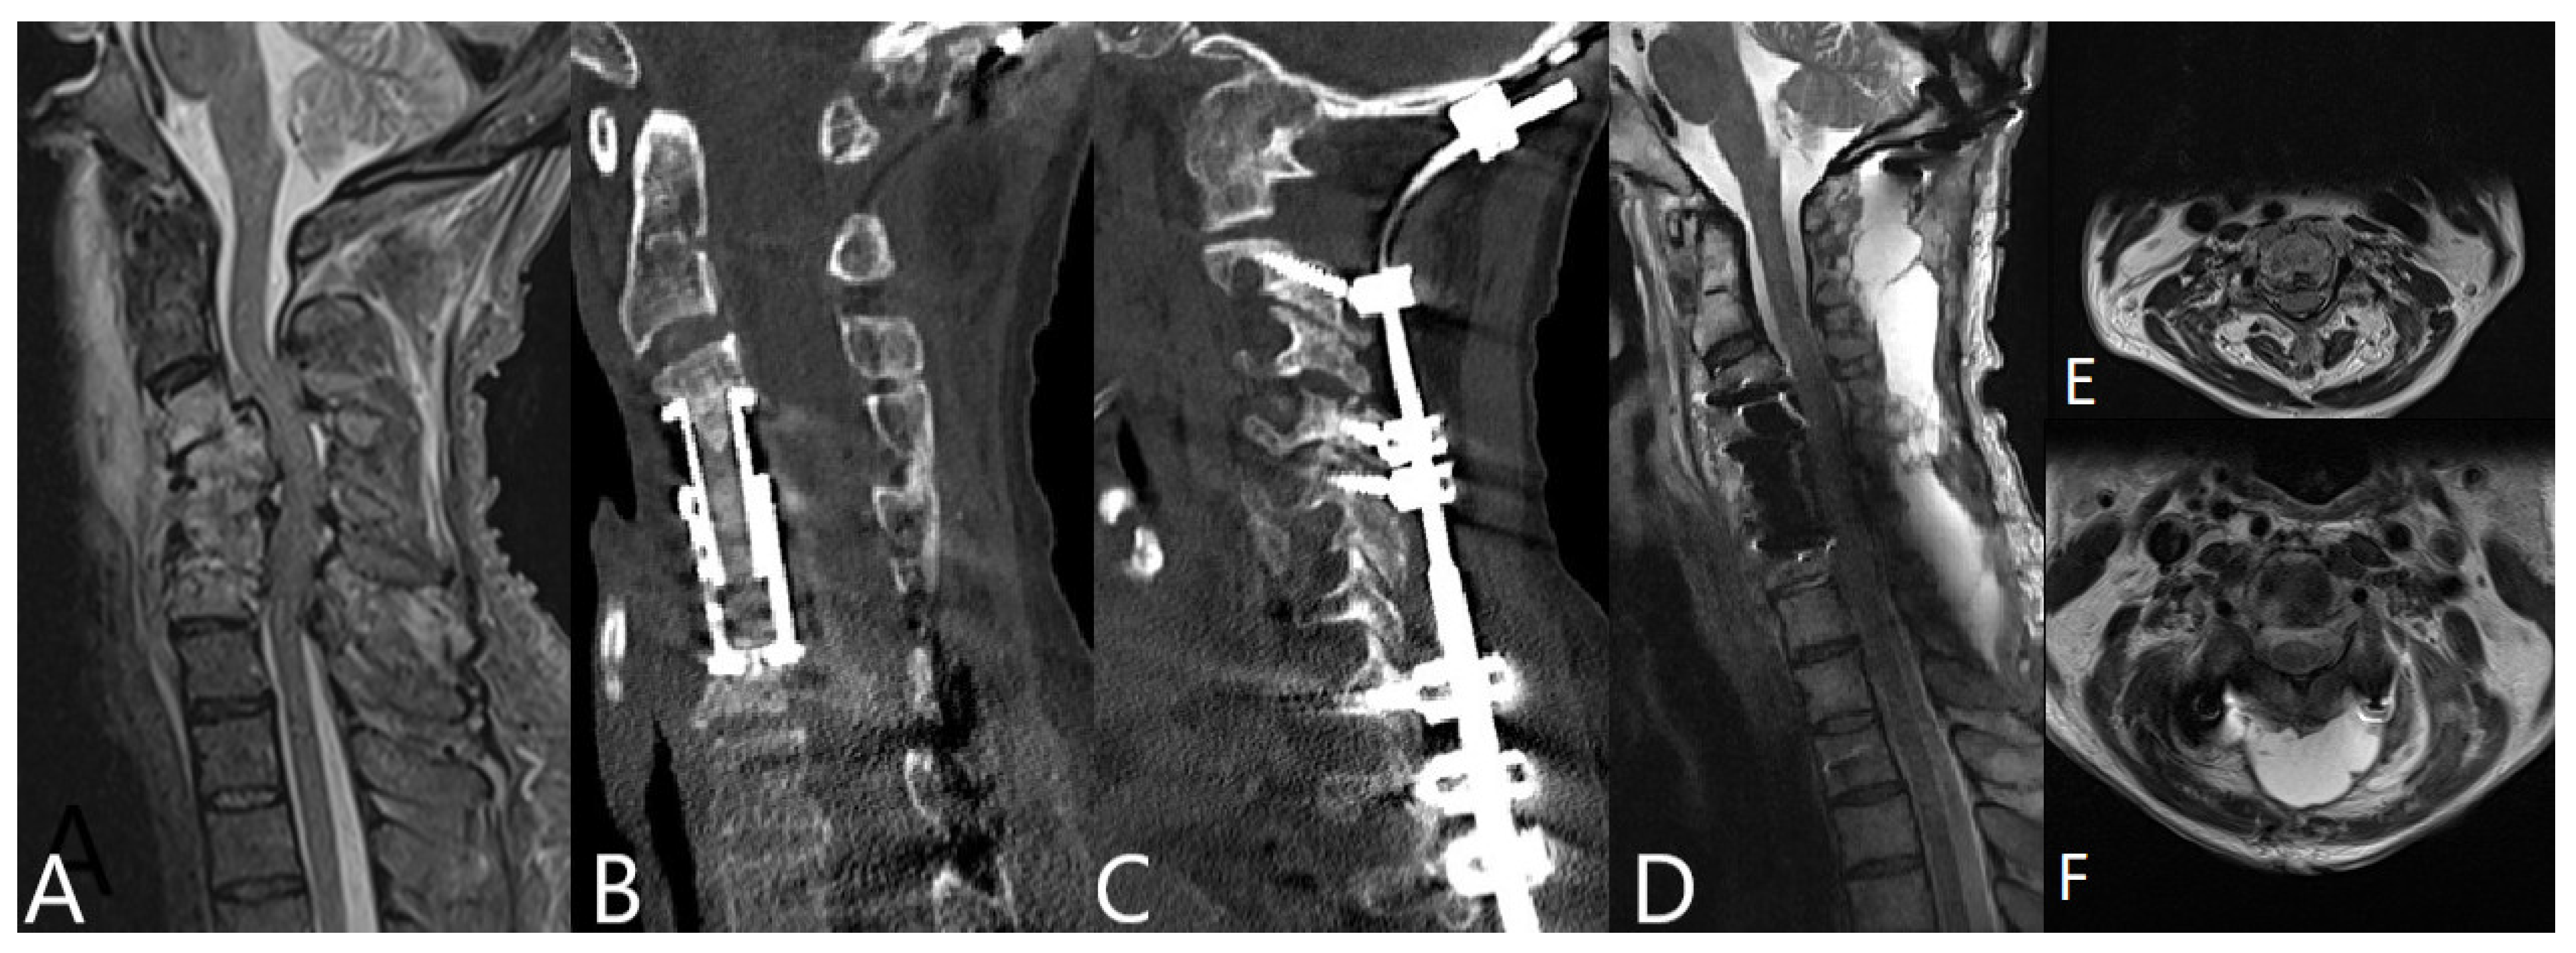

| Cervical spine | 45 |

| Ventral discectomy with PEEK (Polyetheretherketon) cage | 31 |

| Corpectomy with Titanium expandable cage | 14 |

| Additional dorsal stabilization | 23 |